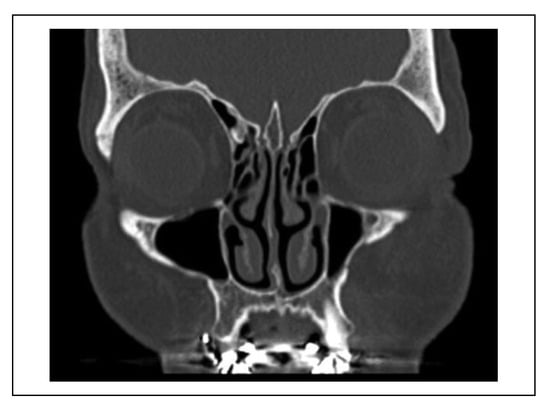

A case was considered to show involvement of the fracture course through the infraorbital canal (IOC) when the fracture line penetrated the cortex of the IOC at one site or more (Figure 2). When the fracture line was near the IOC (within 1 mm), this indicated that the cortex of the IOC was still intact (Figure 3).

Figure 3. Patient with a left zygomaticomaxillary complex fracture with the fracture line near the infraorbital canal (within 1 mm), and an intact cortex of the infraorbital canal. This patient did not experience hypoesthesia of the infraorbital nerve.